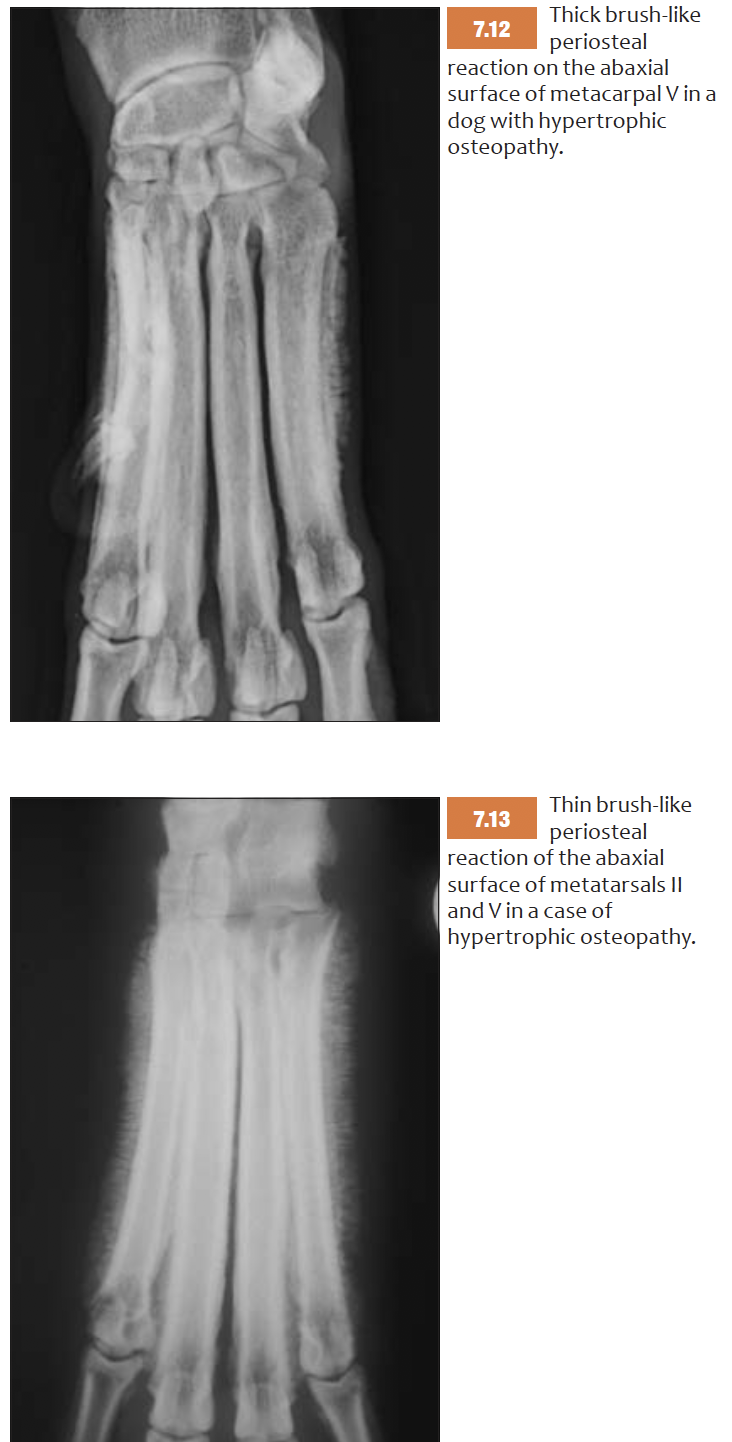

List features of brush like periosteal reaction

E.g osteomyelitis, neoplasia, hypertrophic osteopathy